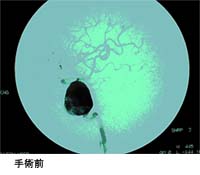

直径2.5cmより大きい動脈瘤を巨大脳動脈瘤と言います。巨大脳動脈瘤の治療は以下のような理由で治療が困難です。巨大であるため、1個のクリップで完全に動脈瘤を消失させることが困難です。

動脈瘤内部に血栓(血の塊)が存在していることが多く、クリッピング術の際に、血栓が破綻して流れ出し正常血管内に詰まると脳梗塞を起こす可能性があります。巨大であるため、正常血管が動脈瘤本体から分岐していることが多く、クリッピング術の際に正常血管を温存することが困難です。

無理であれば動脈瘤頚部のクリッピングに拘らず、以下に示しました血管吻合術を利用して正常血管の血流を維持したうえで、動脈瘤の前後で血流を遮断し破裂しないようにします。巨大脳動脈瘤の治療は、一筋縄ではいかないことが多いのですが、私たちは様々な方法を用いて治療しています。 動脈瘤に入る血管を結紮して閉塞し、脳の血流はバイパスの血管にて流れています。